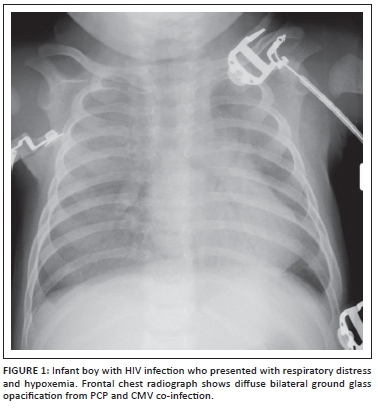

Pneumonia remains the most common cause of hospital admission in African children infected with HIV. Pneumonia related mortality in children infected with HIV is currently 3-6 times that of non-HIV infected patients.5Pneumocystis jirovecii (PCP) pneumonia remains a frequent underlying infectious cause in infants infected with HIV. These affected infants typically present with mild to severe acute respiratory distress and hypoxia.5 Superimposed infection with Cytomegalovirus (CMV) in HIV infected infants with PCP pneumonia is common and results in more rapid progression of underlying HIV disease.5,6 The common respiratory viruses of childhood (respiratory syncytial virus, influenza, parainfluenza and adenovirus) are more common in older children with HIV and are more likely to be complicated by bacterial pneumonia.4

In infants with PCP and/or CMV, the radiograph usually demonstrates varying degrees of ground glass opacification that may be symmetrical or asymmetrical (Figure 1). Short term complication such as air-leaks or long term complication such as cystic lung change (e.g., pneumatocele formation) (Figure 2) may also subsequently develop.